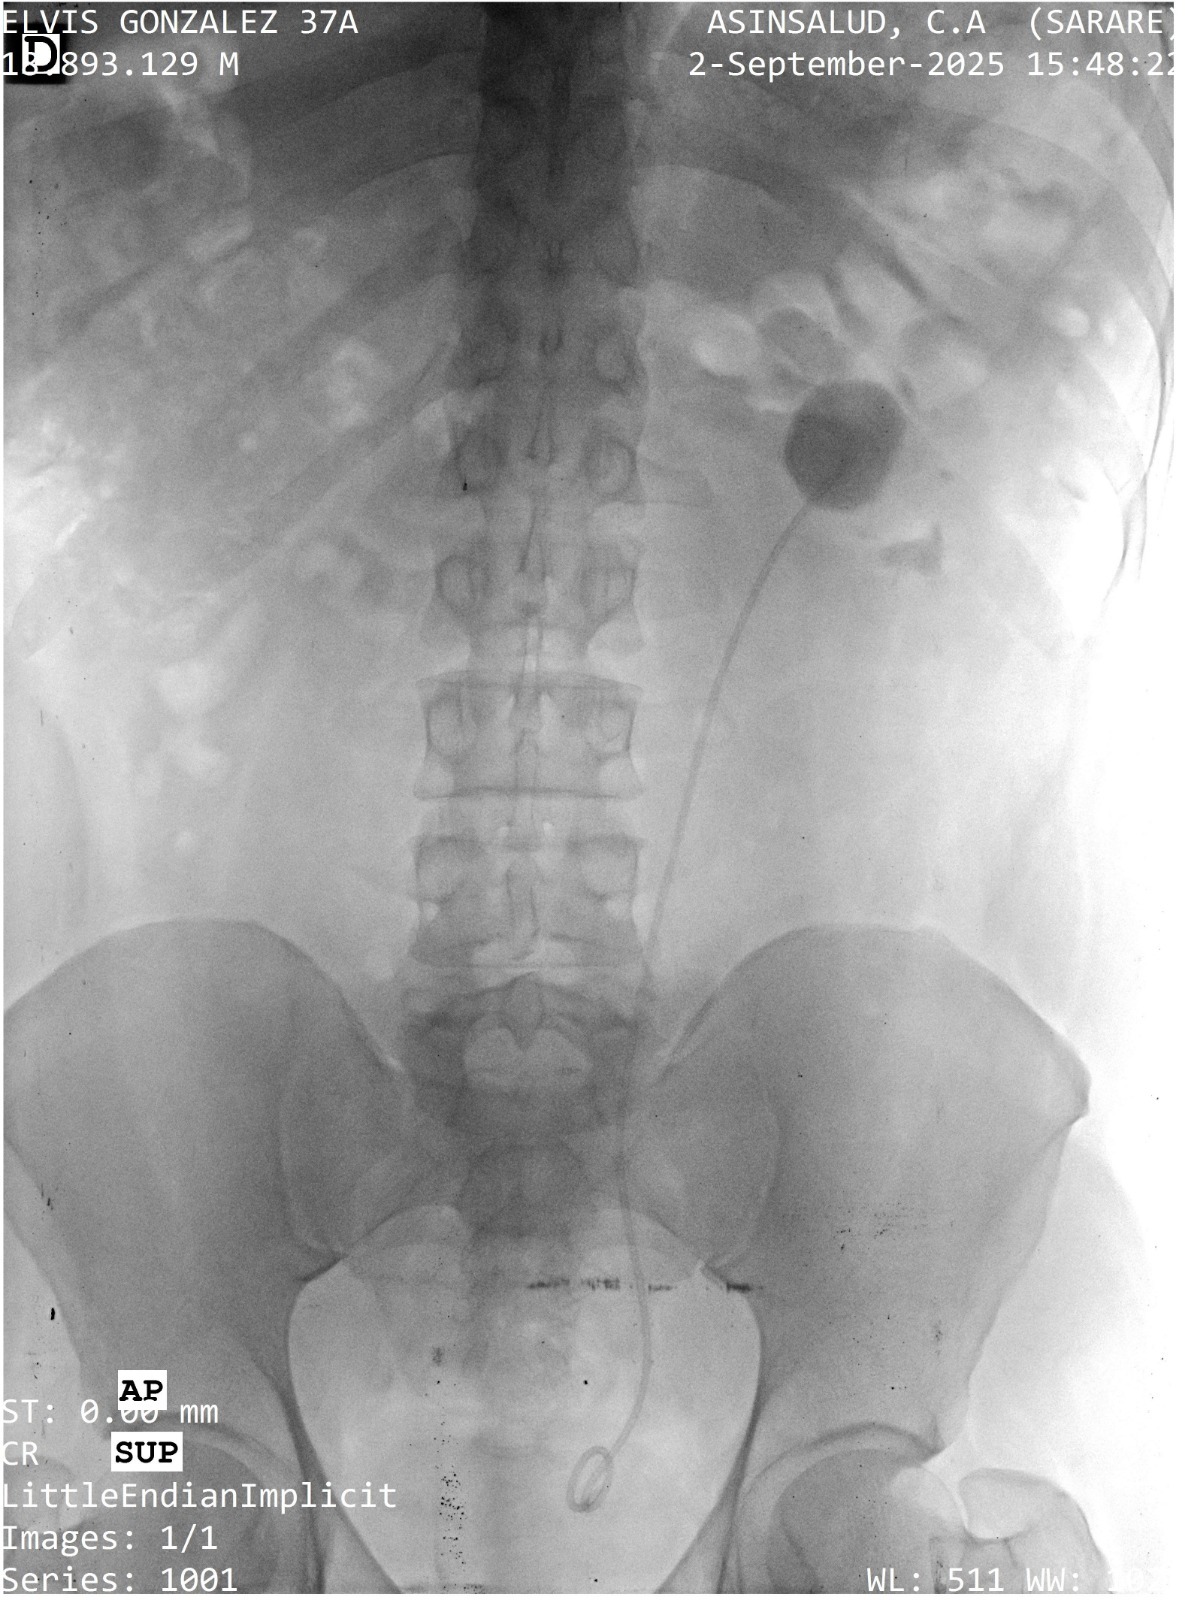

Mi tío tiene 37 años, es padre de familia, un hombre trabajador y muy humilde. Desde hace un tiempo viene sufriendo por un cálculo en el riñón izquierdo, y la situación se ha complicado: hoy está hospitalizado en Venezuela, con mucho dolor, y necesitamos actuar lo más pronto posible.

Para aliviar la obstrucción y el dolor, los médicos le colocaron un catéter temporal, pero esto no resuelve el problema. La solución real es una cirugía con láser para retirar el cálculo y evitar que el riñón siga empeorando. Si se retrasa, existe el riesgo de que el riñón se afecte de forma permanente y su vida cambie por completo.